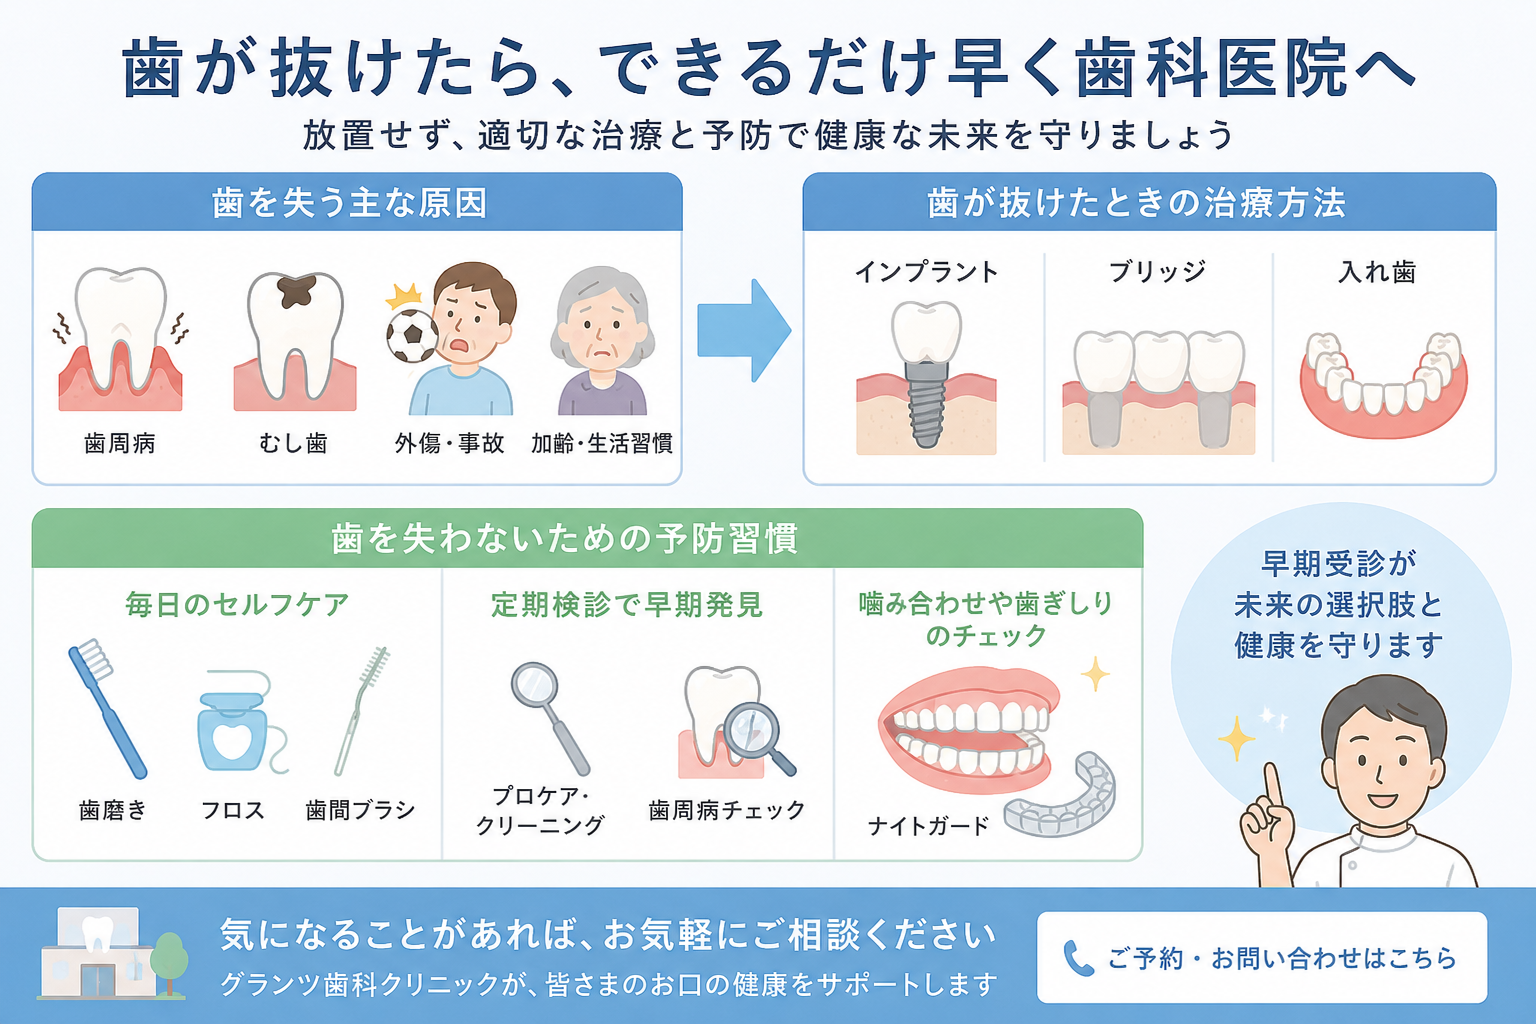

グランツでは、患者様の理想を叶えることを目的に、機能的にも審美的にも回復する質の高い治療をしております。お一人お一人によってベストは異なりますので、まずはお電話にて、ご相談ください。